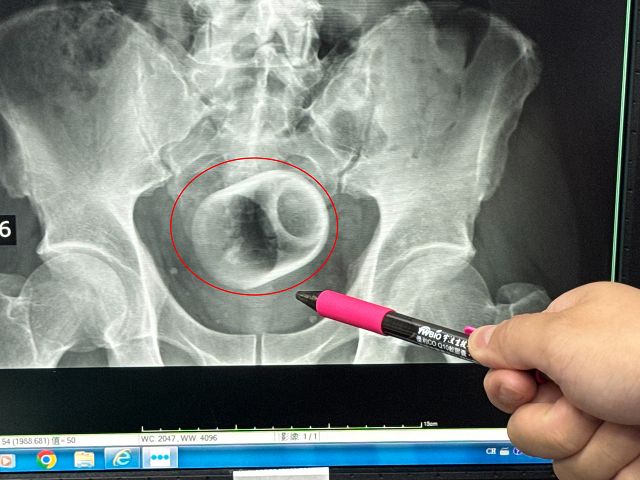

駐診在李綜合醫院的台中榮總外科醫師吳坤達表示,該名患者到院時,自訴三天無法大便非常困擾,害羞不敢提及自己肛門塞了一個杯子,經過X光攝影,看到骨盆腔內有一個杯子,杯口朝下,因此,馬上安排進手術室,要把杯子拿出來。

吳坤達說,一開始試著使用器械直接把杯子夾出來,但是杯子光滑,用了很多器械,試了很多次都無法成功,後來再使用腹腔鏡,依舊無法順利取出,擔心把杯子夾碎,傷及患者或造成感染風險,最後只好在肚子上動刀,直接「破肚開腸」劃開腸子,總共花了兩個多小時,才順利取出杯子,同時做了一個人工造口,讓患者能夠暫時解便。